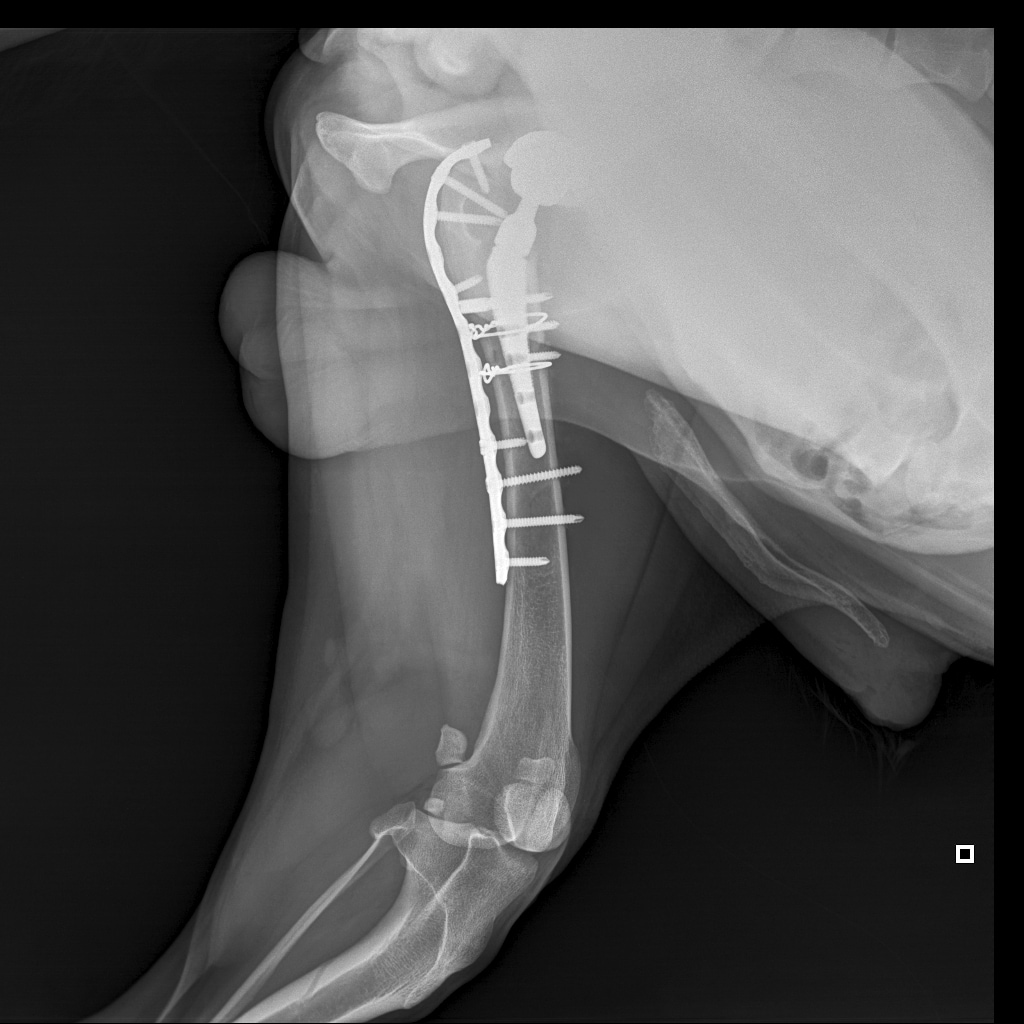

8A836050-66CA-42B2-94D3-F13B288A592B.jpeg

39B2671E-39B9-4502-9E11-ADB169612F24.jpeg

6950B9C9-79EA-4F34-A780-9C3C6BA31B49.jpeg

58C20B18-AA4E-4386-BF83-56CE5E282844.jpeg

Наш металлический мальчик

Железный дровосек